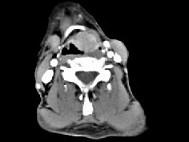

男,53岁,咽部不适半年余,近2个月感咽部疼痛,声嘶,CT如图所示,应诊断为 ( )

答案: D